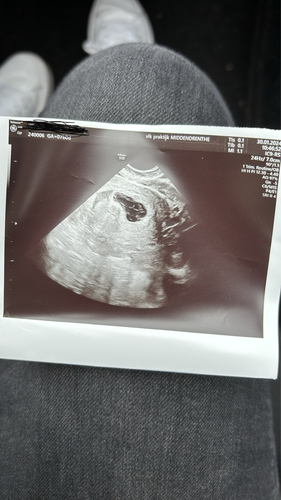

Wij hebben ervoor gekozen om het rustig aan te doen. Nu ben ik heel pril zwanger (spannend!!).